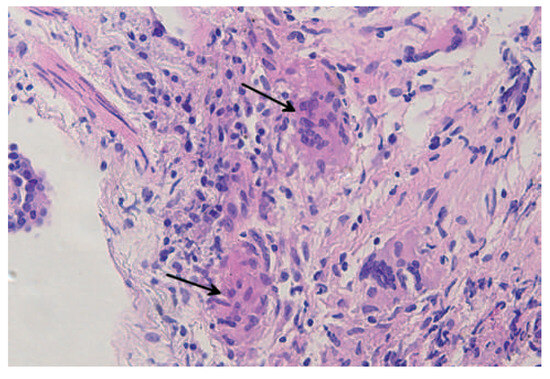

Heart Failure in a Patient with Multi-Organ Sarcoidosis

by Marc Buser, Theresa Dellas Buser, Jens Bremerich and Daniel Tobler

Cardiovasc. Med. 2012, 15(11), 329; https://doi.org/10.4414/cvm.2012.00124 - 21 Nov 2012

Viewed by 147

Abstract

A 53-year-old woman was admitted to our emergency department with progressive shortness of breath during exertion for three months. [...] Full article

Show Figures

Figure 1